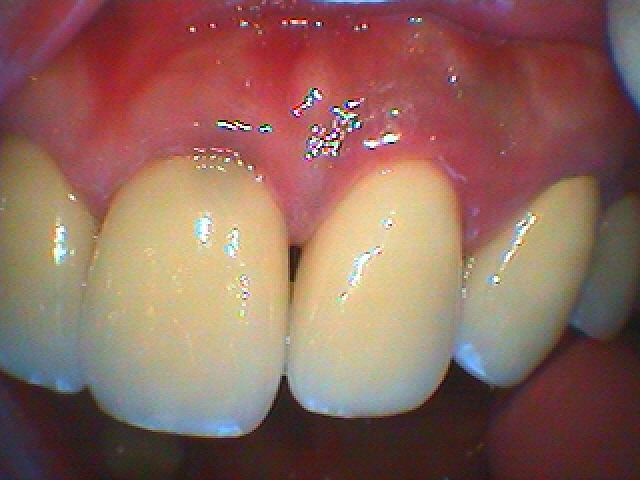

問題の左上の1,2番部になります

口蓋側から見たところにになります

昔、2番部を歯根端切除をされたそうです